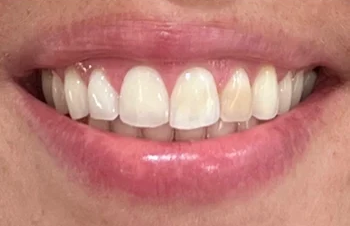

Onlangs bezocht een patiënte van in de dertig onze praktijk. Haar mondgezondheid en mondhygiëne waren uitstekend. Er was maar een ding dat opviel en waar zij niet tevreden over was: frontelement 22 was significant donkerder van kleur

Afbeelding 1: Uitgangssituatie vóór de bleekbehandeling

Bij de eerste kleurbepaling van dit element (22) was er sprake van kleurtint A3.